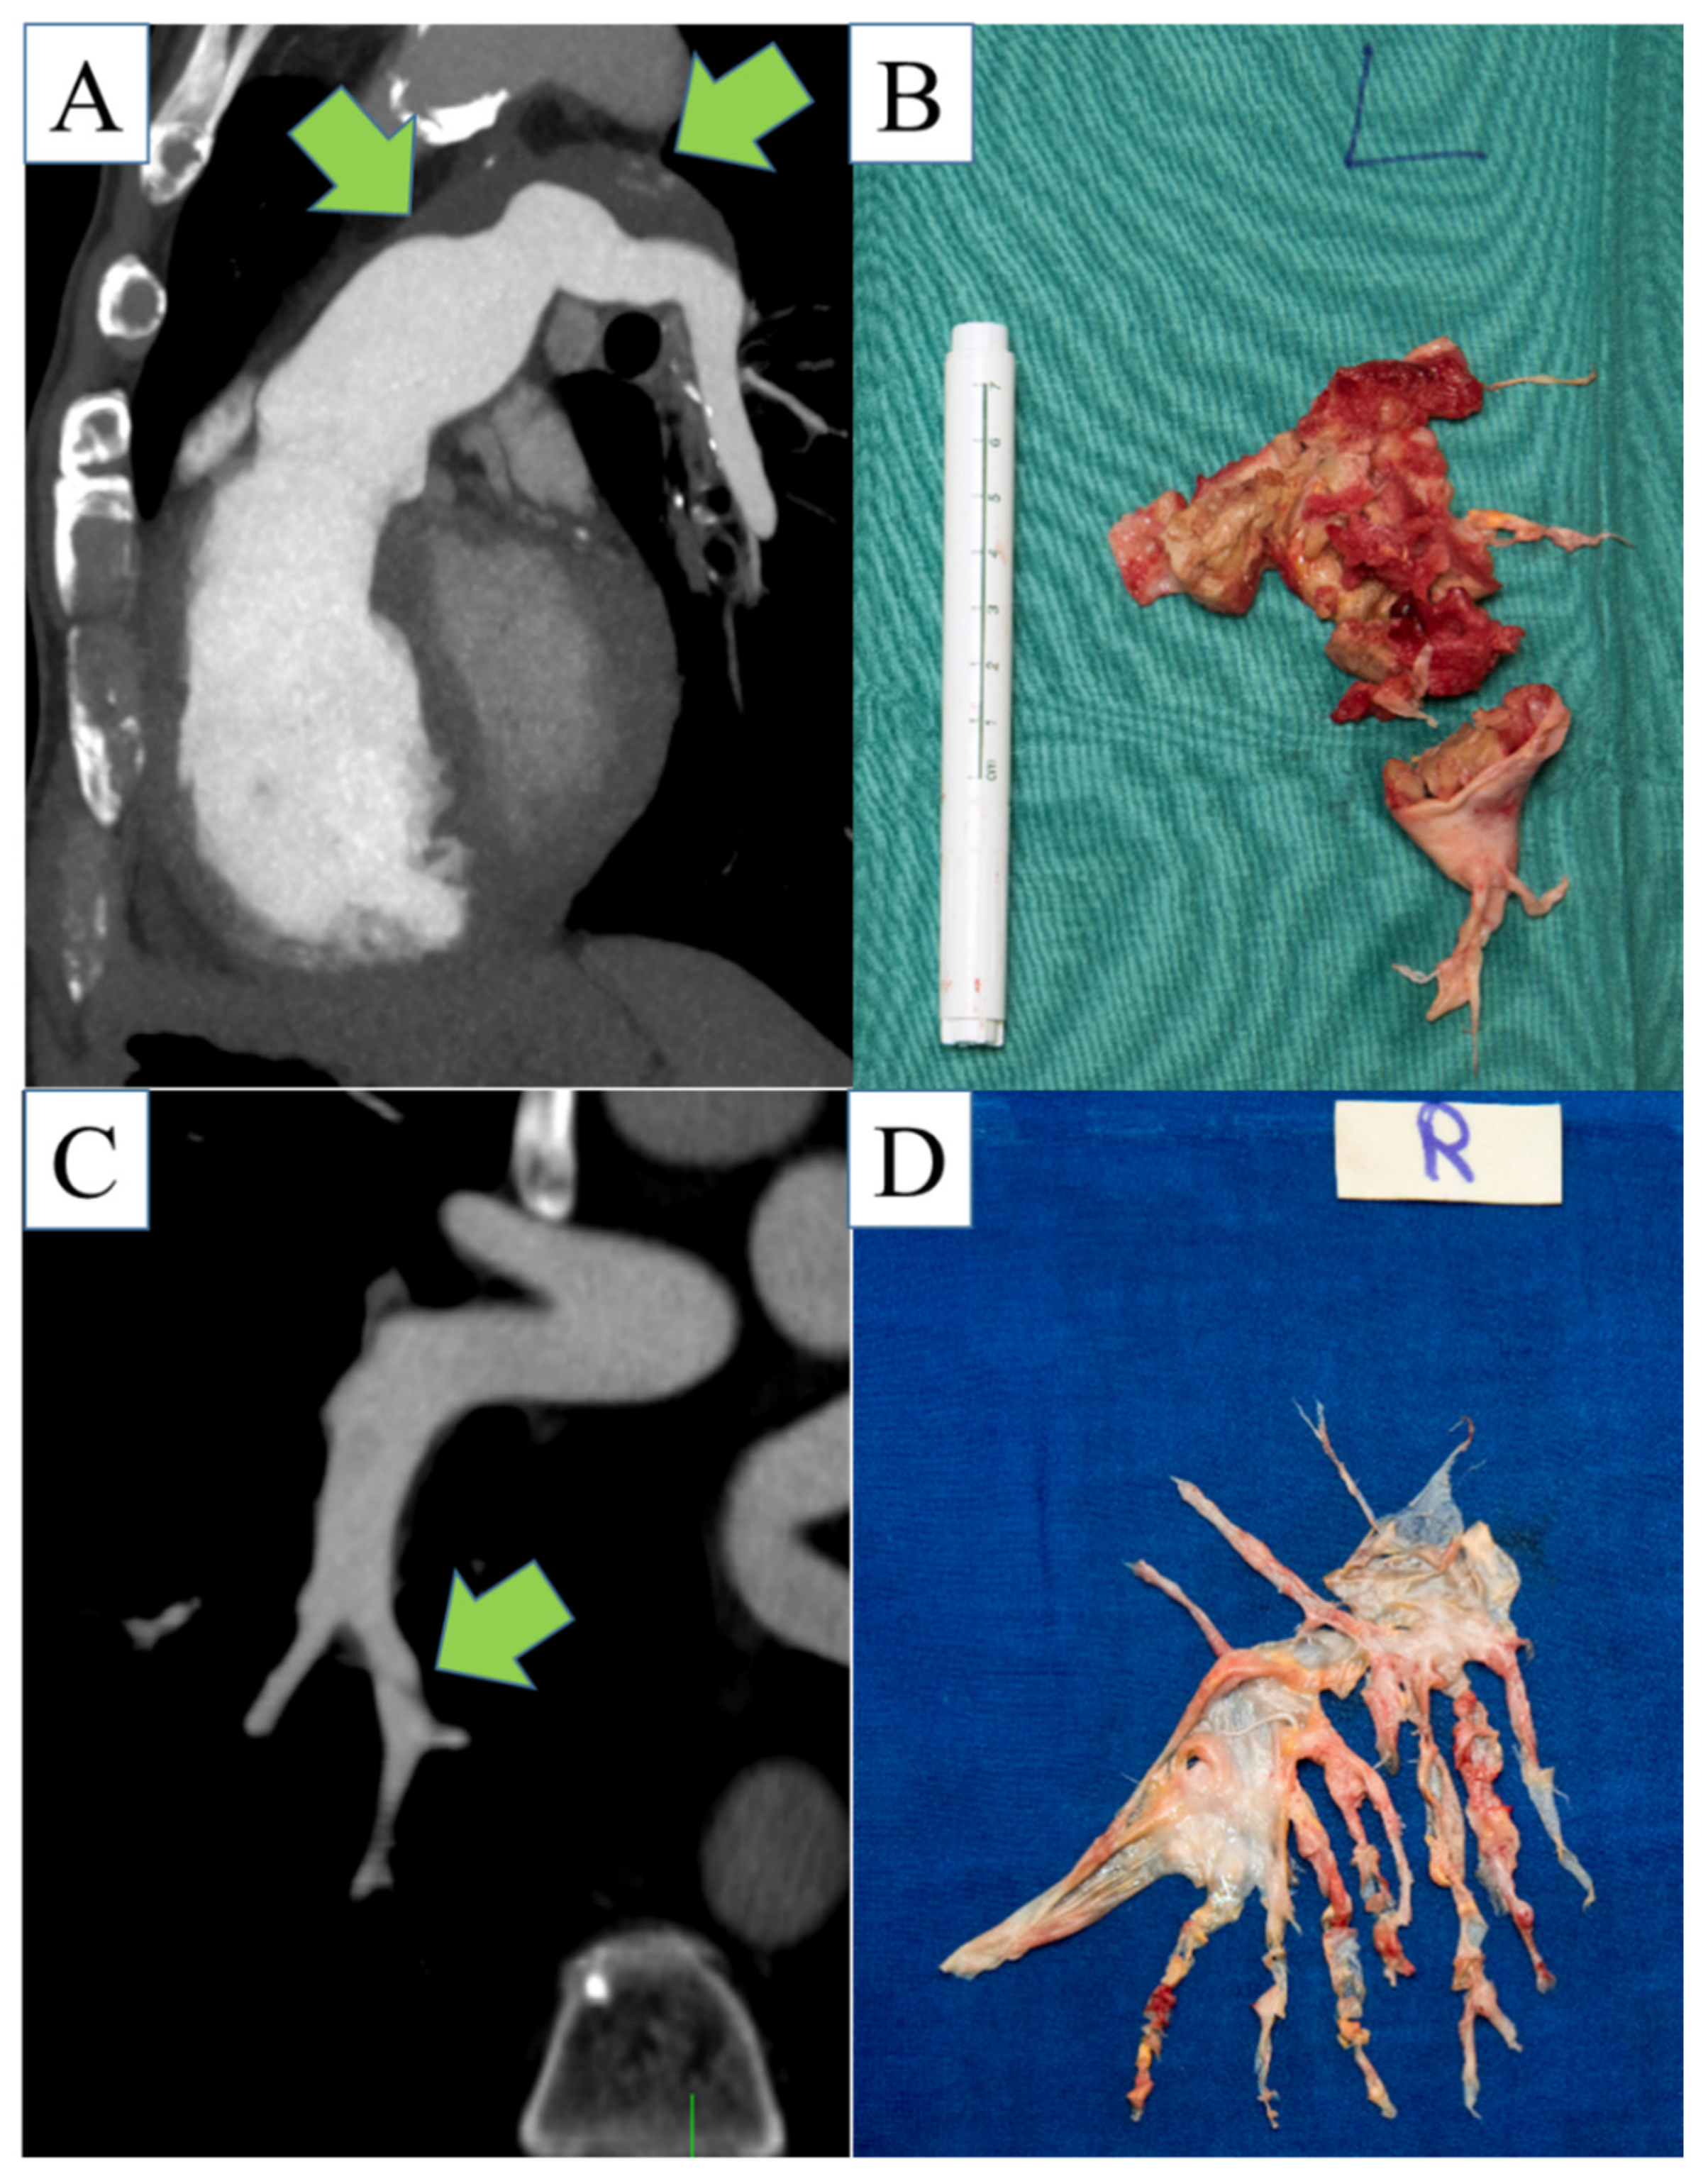

2.3. Analysis of Pulmonary Arteries

3.2. CT Categorization of Thromboembolic Level of Disease

3.2.2. Consensus Classification